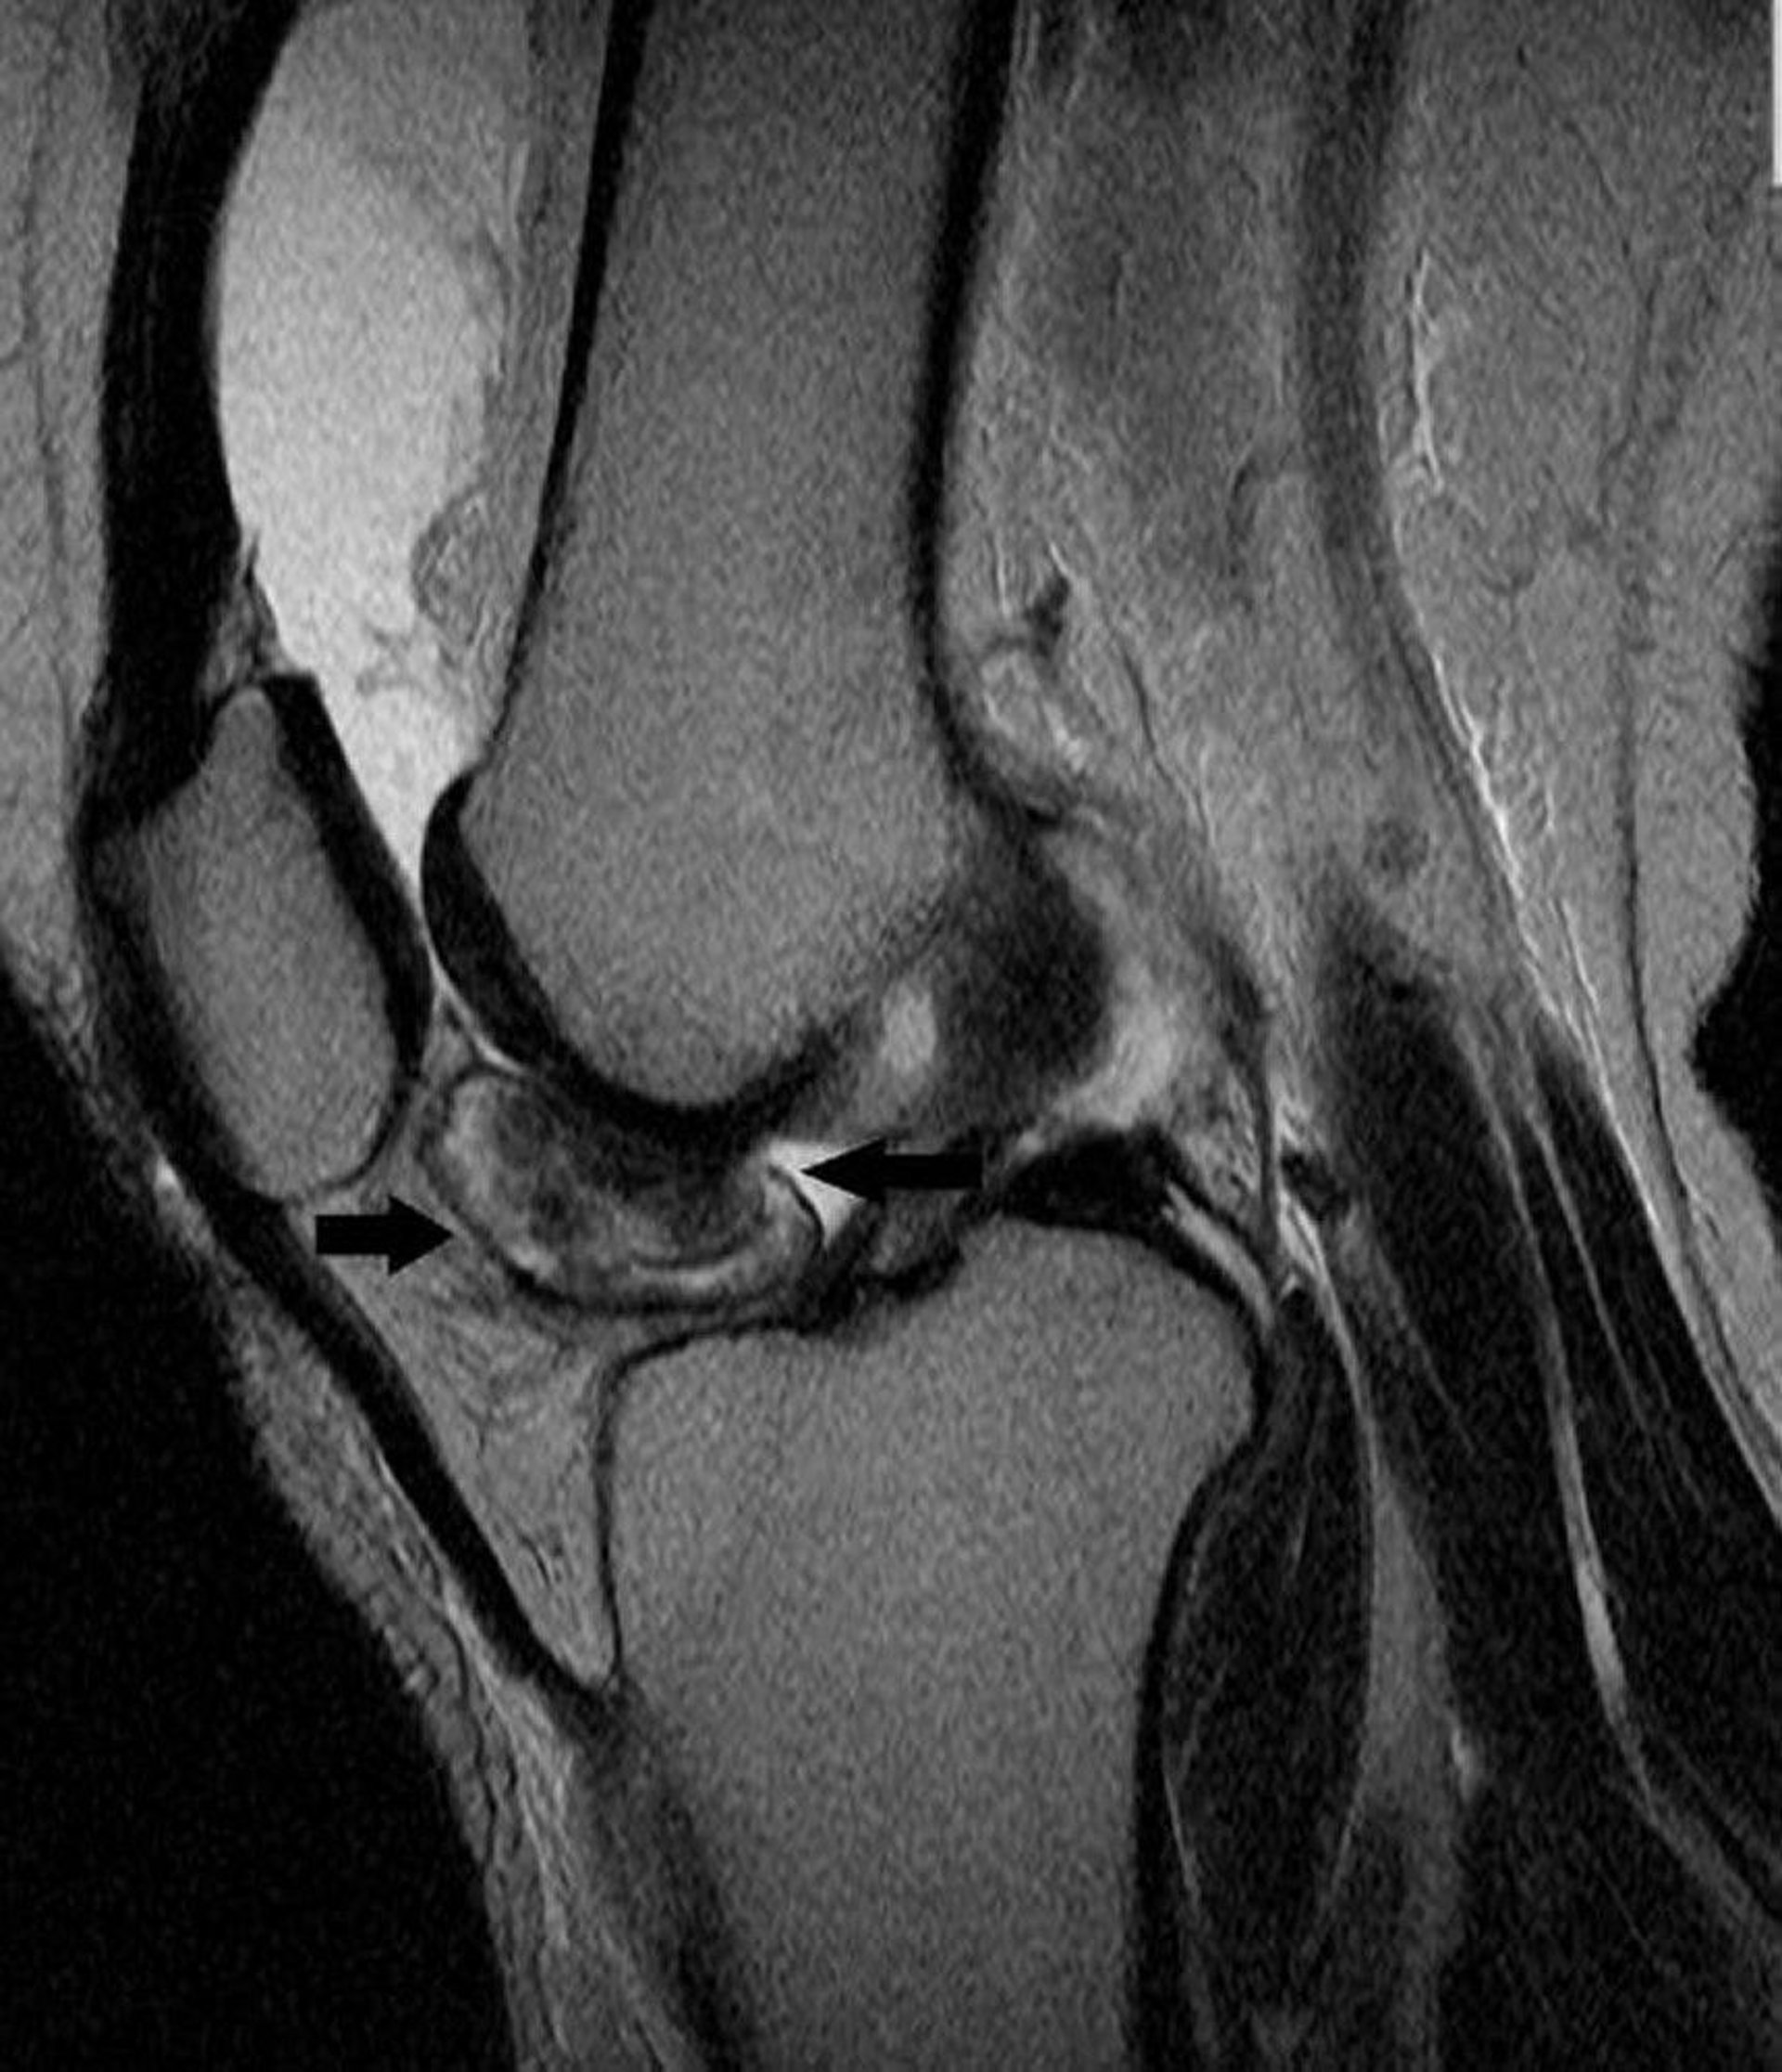

This MRI of the knee shows tenosynovial giant cell tumor in the lining of knee joint (arrows).

Image courtesy of Michael J. Joyce, MD, and Hakan Ilaslan, MD.